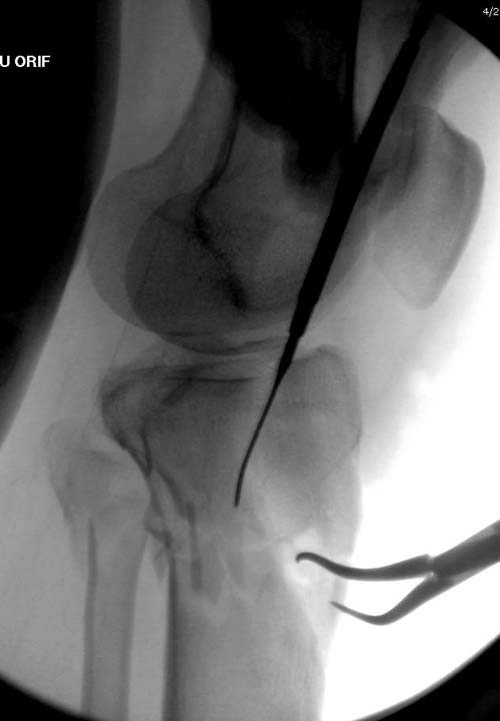

Вытяжение или наружный фиксатор “бедро-голень в виде дельты”. Фиксатор дает свободу, и если условия позволяют, можно отпускать домой. Но главное - надо ожидать проявления “wrinkle sign”! После дистракции можно делать КТ исследование, иначе нестабильные фрагменты искажают данные. Доступ делается по топографии расположения фрагментов, а 3Д картина лучше покажет расположение смещенных мыщелков.

На боковом рентгене, явный задний смещенный компонент. КТ поможет увидеть "вершину" перелома, куда надо поставить антискользящую пластину из заднего или задне-медиальнего доступа. Для стабилизации боковой колонны традиционный боковой доступ через Girdle tubercle с длинной блокирующей пластиной. Одна задняя подпорка не удержит медиальную колонну, требуется длинная медиальная пластина.

Перелом сложный, и для окончательного успеха потребуется арсенал фиксаторов и наличие опыта разных доступов. К успеху приведет только тщательное планирование. Возможно, фиксировать не удастся все за раз. Если во время операции возникнет опасность развития отека в ране, “damage control” операцию надо отложить, лучше поэтапно, чем осложнение.